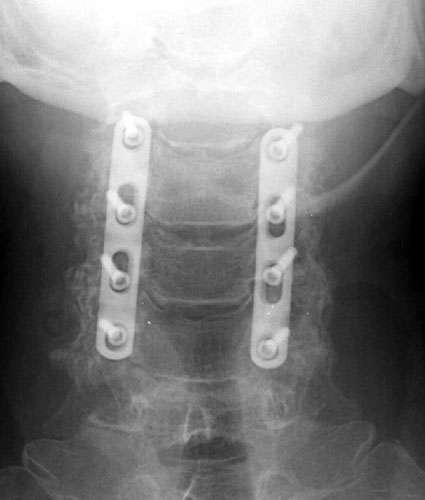

AP and lateral radiographs taken 5 days after surgery demonstrate

typical laminectomy defects at C3-6. The posterolateral fusions appear intact

with bone grafting material faintly appreciated. The screws and plates are

intact and in appropriate positioning. |